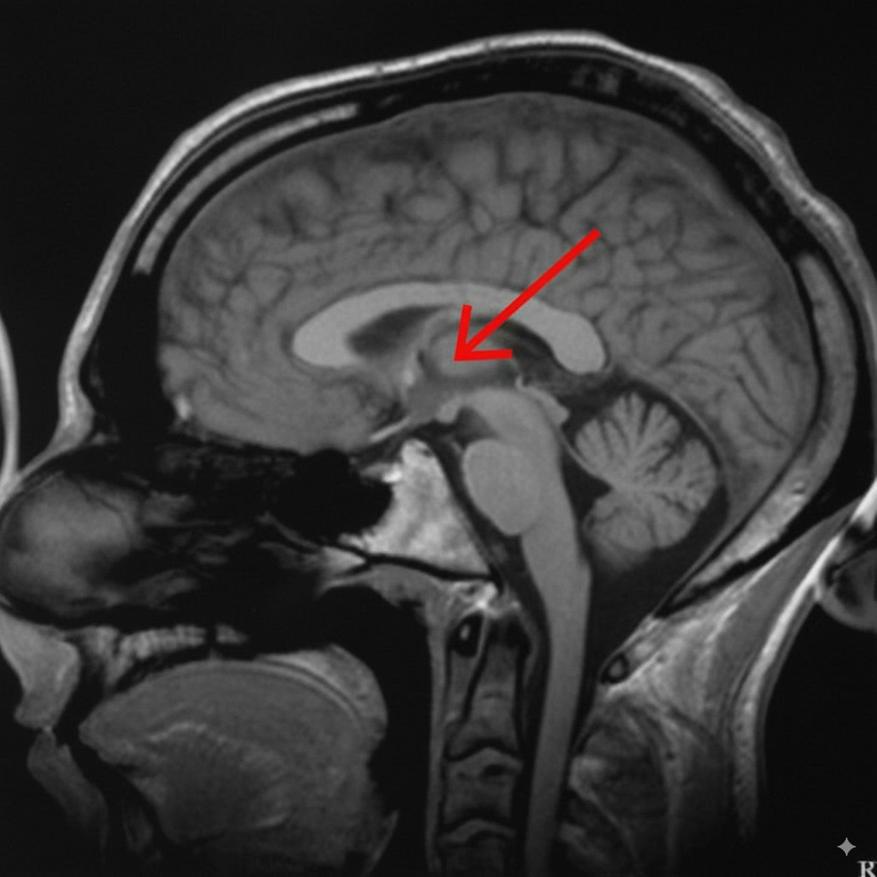

Найдена часть мозга, отвечающая за сознание. Таламус — недооцененная структура, формирующая нашу реальность

Долгое время основное внимание было приковано к коре головного мозга — его знаменитому серому веществу. Но последние исследования указывают на другую, более глубокую и центрально расположенную структуру — таламус.

Новые данные показывают, что таламус — это не пассивный передатчик сенсорных сигналов. Это активная система управления, которая играет решающую роль и в поддержании общего состояния бодрствования, и в формировании конкретного содержания нашего восприятия. Разберем, как именно он это делает.

Таким образом, таламус предстает не пассивным посредником, а динамической системой управления. Он использует разные типы нейронов для двух ключевых задач: поддержания общего состояния бодрствования и формирования конкретного содержания нашего опыта.

Фундаментальный вывод заключается в том, что сознание — это не продукт одной лишь коры головного мозга. Это результат сложного и непрерывного взаимодействия между корой и таламусом, где каждая из структур выполняет свою незаменимую роль.